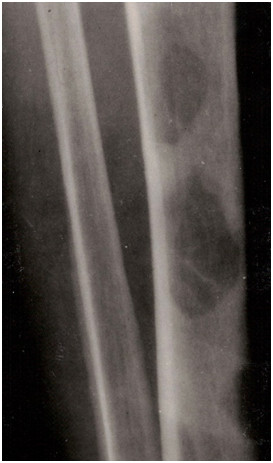

Uwidocznione na zdjęciu RTG zmiany są najbardziej charakterystyczne dla: